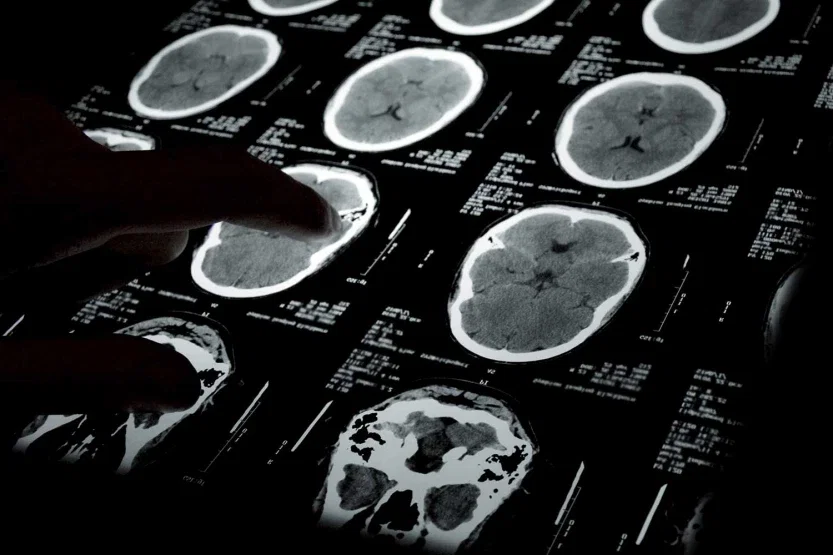

Cancer misdiagnoses can result from several medical mistakes made by doctors. Some cancers are detectable with screening tests. If those tests are performed incorrectly or misinterpreted by medical personnel or radiologists, evidence of cancer may be missed, resulting in a delay in diagnosis.

The diagnosis of other types of cancer may be delayed because tests or scans aren’t done until the patient makes repeated trips to the doctor with the same complaint. By then, the cancer may have metastasized, and the patient’s life could be threatened. A careful review of medical records may show evidence of cancer in earlier X-rays, scans, or slides. If the cancer had been treated then, there may have been a better outcome.